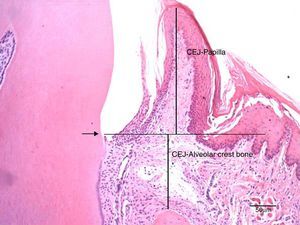

The cuts were stained with hematoxylin and eosin according to the routine protocol used at the Histologic Laboratory of the Universidade do Sagrado Coração. Three equidistant histologic sections were selected per tooth for the histometric analysis. The sections were digitalized at 100× magnification (10× objective lens and 10× ocular lens). Using the linear measuring system (Image-Pro®, Media Cybernetics, Silver Spring, MD, USA), we measured the distance from the free gingival margin (FGM) to the cemento-enamel junction (CEJ) to evaluate the gingival recession, and, also, the distance from CEJ to the reminiscent alveolar crest (Fig. 2). The measures were carried out on the mesial surface of the mandibular first molar and they were expressed in micrometers (μm).

Photomicrography at 100× magnification (10× objective and 10× ocular) of the mesial region of the mandibular first molar. It shows the measurements of the distance from the cemento-enamel junction to the papilla (CEJ-papilla) and the cemento-enamel junction to the bone crest. Arrow: cemento-enamel junction (CEJ); Bar: 50μm.